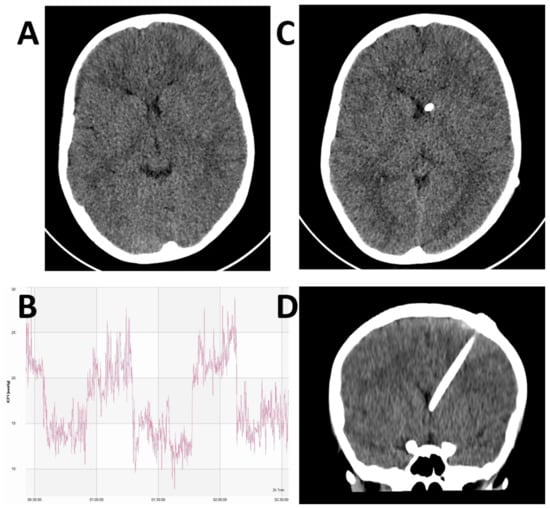

Figure 1. Illustrative case of a 9-year old boy presenting with chronic headaches and visual disturbance. Examination revealed bilateral papilloedema. The initial CT did not demonstrate a pathological mass lesion, but did show characteristic small ventricles (A). Lumbar puncture was equivocal with an opening pressure of 25 cmH2O. Pre-shunt invasive ICP monitoring demonstrated characteristic pathological plateau waveforms (B). A VP shunt was placed under EM guidance. Post-operative axial (C) and coronal (D) CT demonstrated satisfactory position of the ventricular catheter within the frontal horn of the left lateral ventricle.